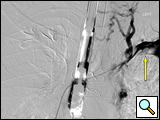

General anesthesia is utilized. Due to the patient's upper airway swelling from SVCS, airway access may be difficult, often necessitating the use of fiberoptic intubation. The patient is positioned supine with both arms placed at 90 degrees. Both arms are prepped in as well as both groins for access. Large bore IV access may be a problem secondary to the extensive upper extremity venous collaterals. Use of the SonoSite Ultrasound® (SonoSite Inc. Bothell, WA) for deep venous access of the upper extremities may be warranted. Two short 6F sheaths placed in the right and left cephalic veins (or one placed in the upper extremity and one in the groin via the common femoral vein) are necessary for access. A soft angled Glide catheter is necessary to access the great veins of the upper mediastinum down to the superior vena cava, and a soft angled Glide catheter placed into the SVC is necessary for performing the contrast venogram of the upper extremities and SVC to localize and define the extent of clot (Figures 2A and 2B).

Figure 2A: AP venogram of left subclavian vein from the right groin catheter demonstrating extensive intravascular clot at the arrow and catheter tips.

Figure 3: AP completion venogram on day 2 after mechanical thrombolysis and TPA infusion overnight and post-deployment of overlapping "kissing" Wallstents. Notice improved drainage into the right atrium on post-deployment venogram.

Re-imaging the following day or twelve hours later is necessary with the objective being bilateral upper extremity venograms showing a significant improvement in venous thrombosis and clot burden. Placement of two self-expanding Wallstents (Boston Scientific Inc., Natick, MA) stents centrally utilizing a "kissing stent" deployment technique [16] is warranted to avoid compression of the contralateral vessel and prevent compression of the flow channel: a 20 mm x 40 mm stent in the superior vena cava and right subclavian vein and a 14 mm x 40 mm stent in the innominate vein and superior vena cava (Figure 3). Stent sizes are selected according to patients' needs.